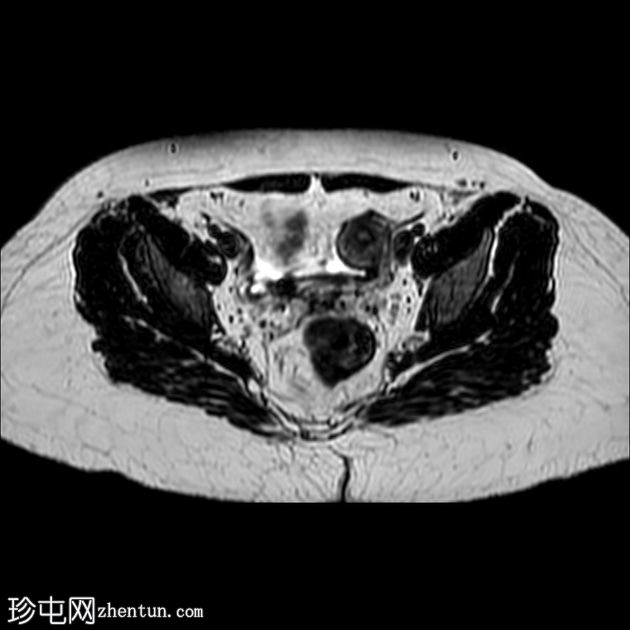

轴位

T1加权像

轴位T2加权像

薄层扫描

盆腔两侧可见两个残角,位于双侧卵巢尾侧。可见一条水平带连接两个残角。左侧残角呈腔状,右侧残角呈非腔状。

可见宫颈阴道发育不全,从两个残角延伸出少量发育不良的宫颈组织带。

双侧卵巢功能正常,可见卵泡。

本病例展示了一种 Mayer-Rokitansky-Küster-Hauser 综合征 (MRKH),其特征为子宫缺失和双侧残角;左侧子宫角呈腔状,右侧子宫角呈非腔状。子宫角位于盆腔两侧,双侧卵巢尾侧,并由一条水平带连接。该病伴有宫颈阴道发育不全。